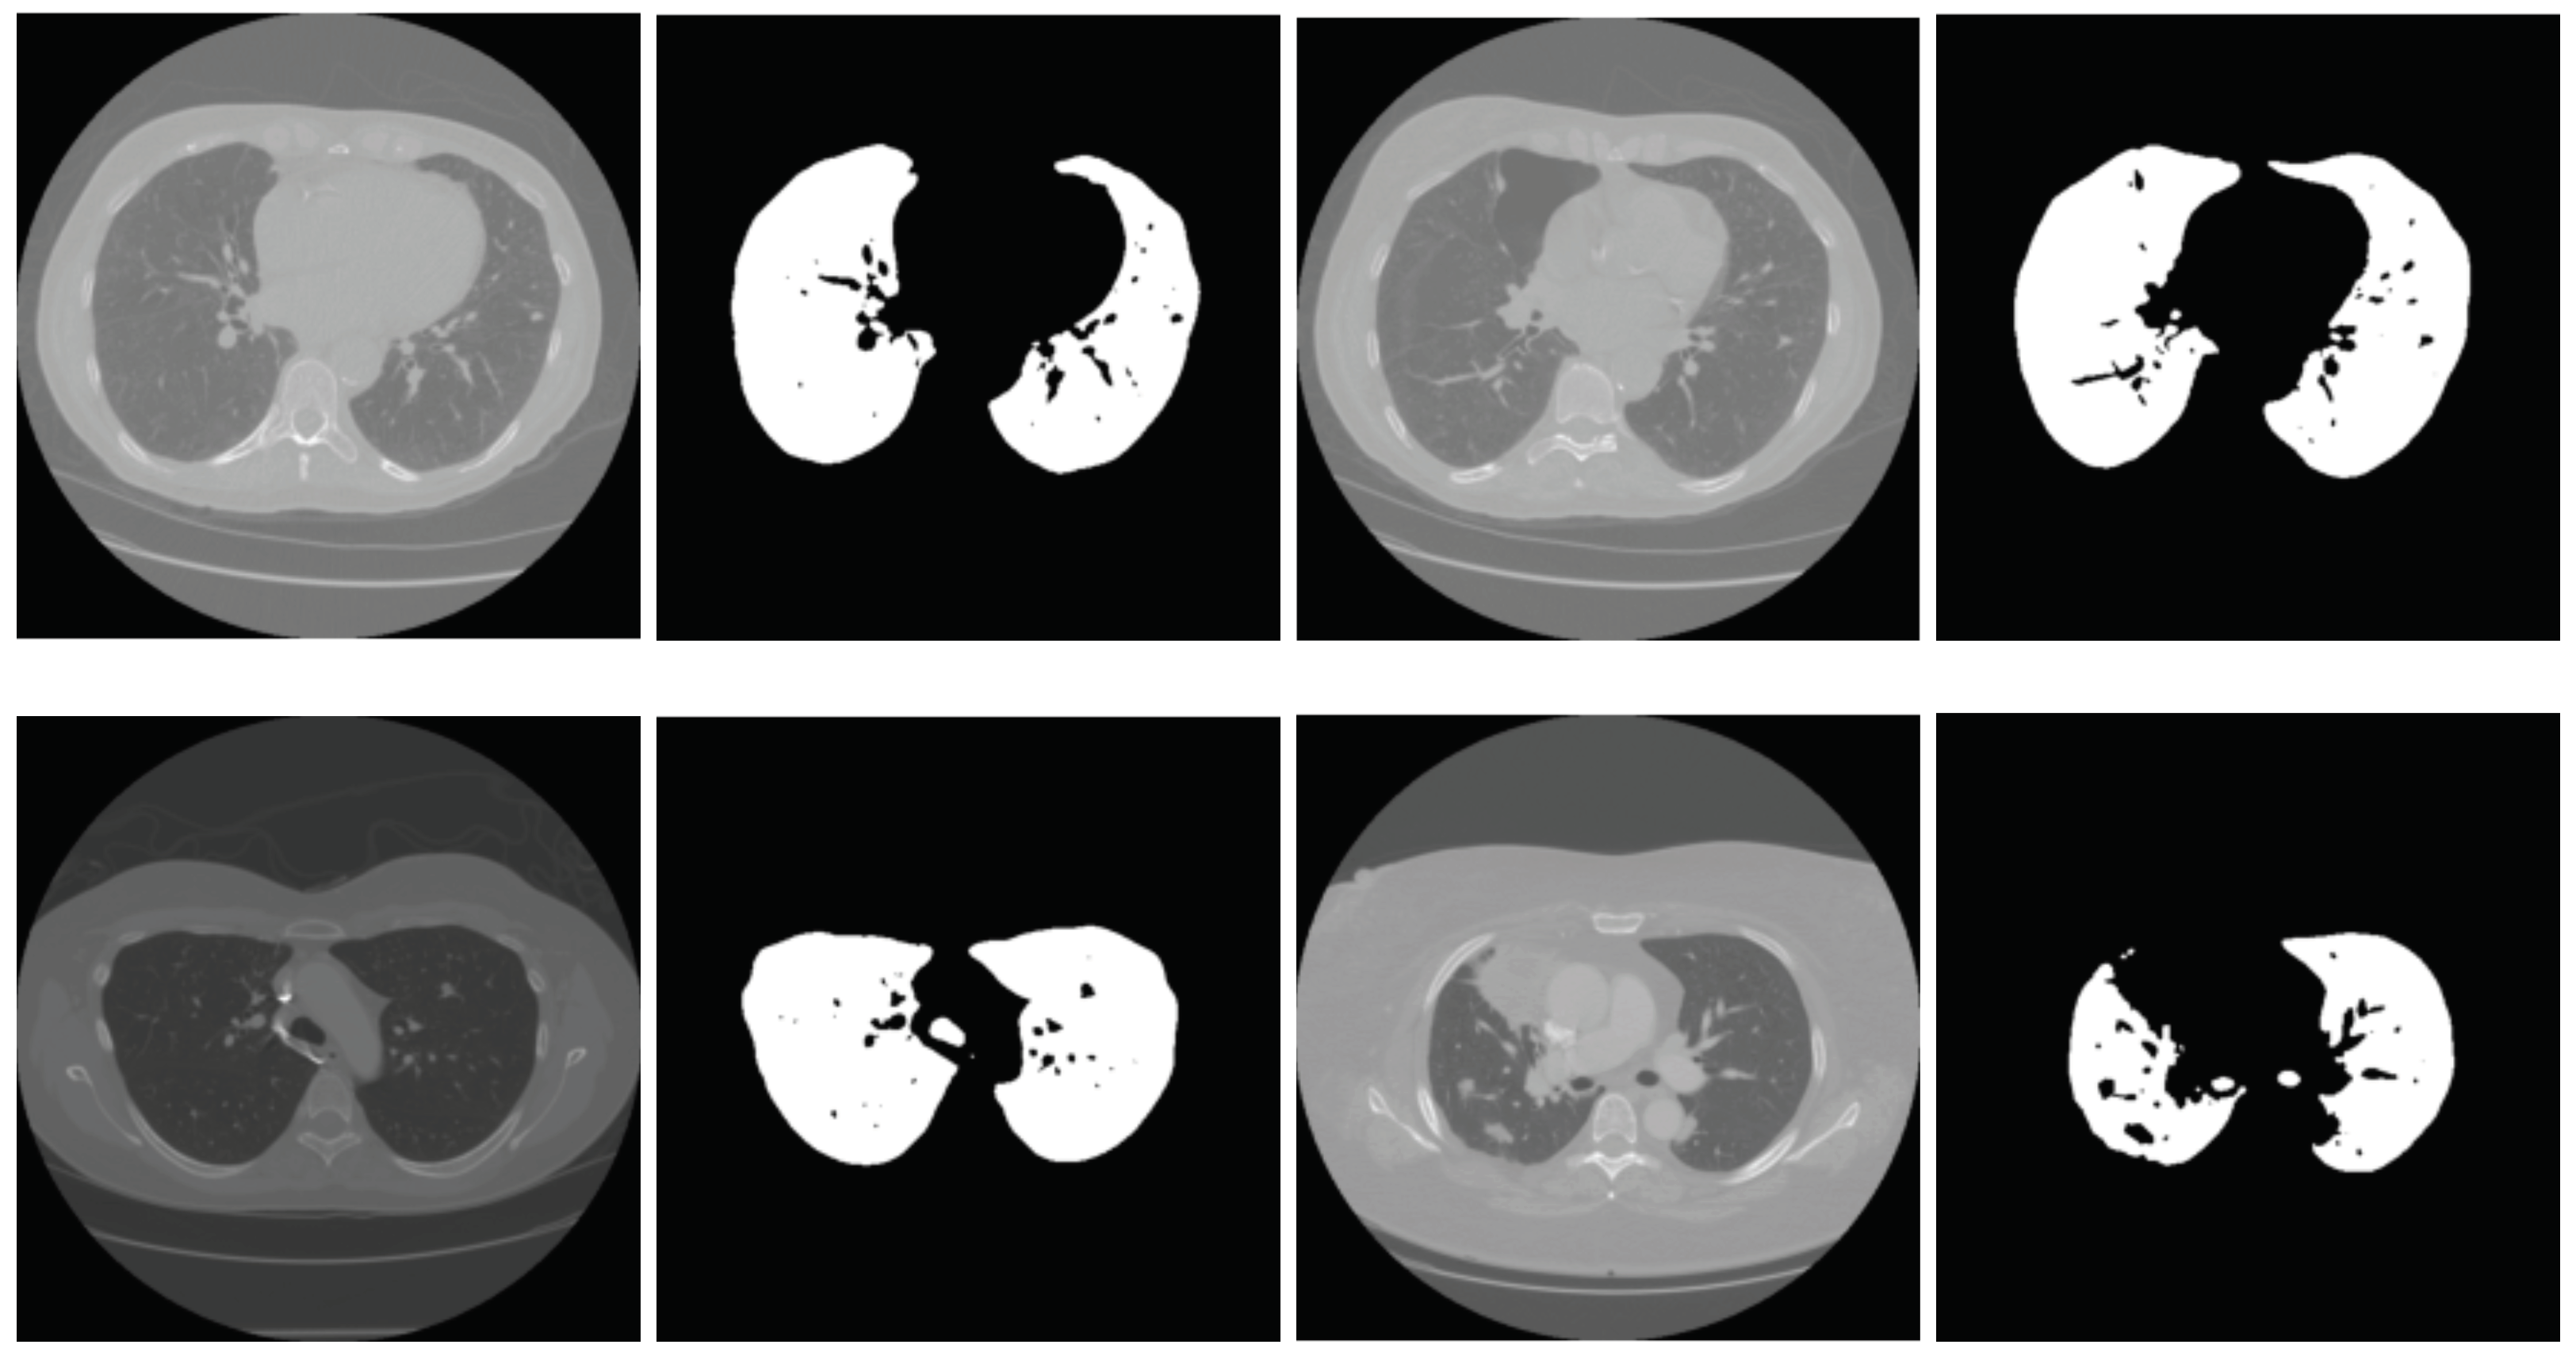

2.2. Lung Segmentation

2.2.1. Segmentation in Lung Window

2.2.2. Segmentation in Mediastinal Window